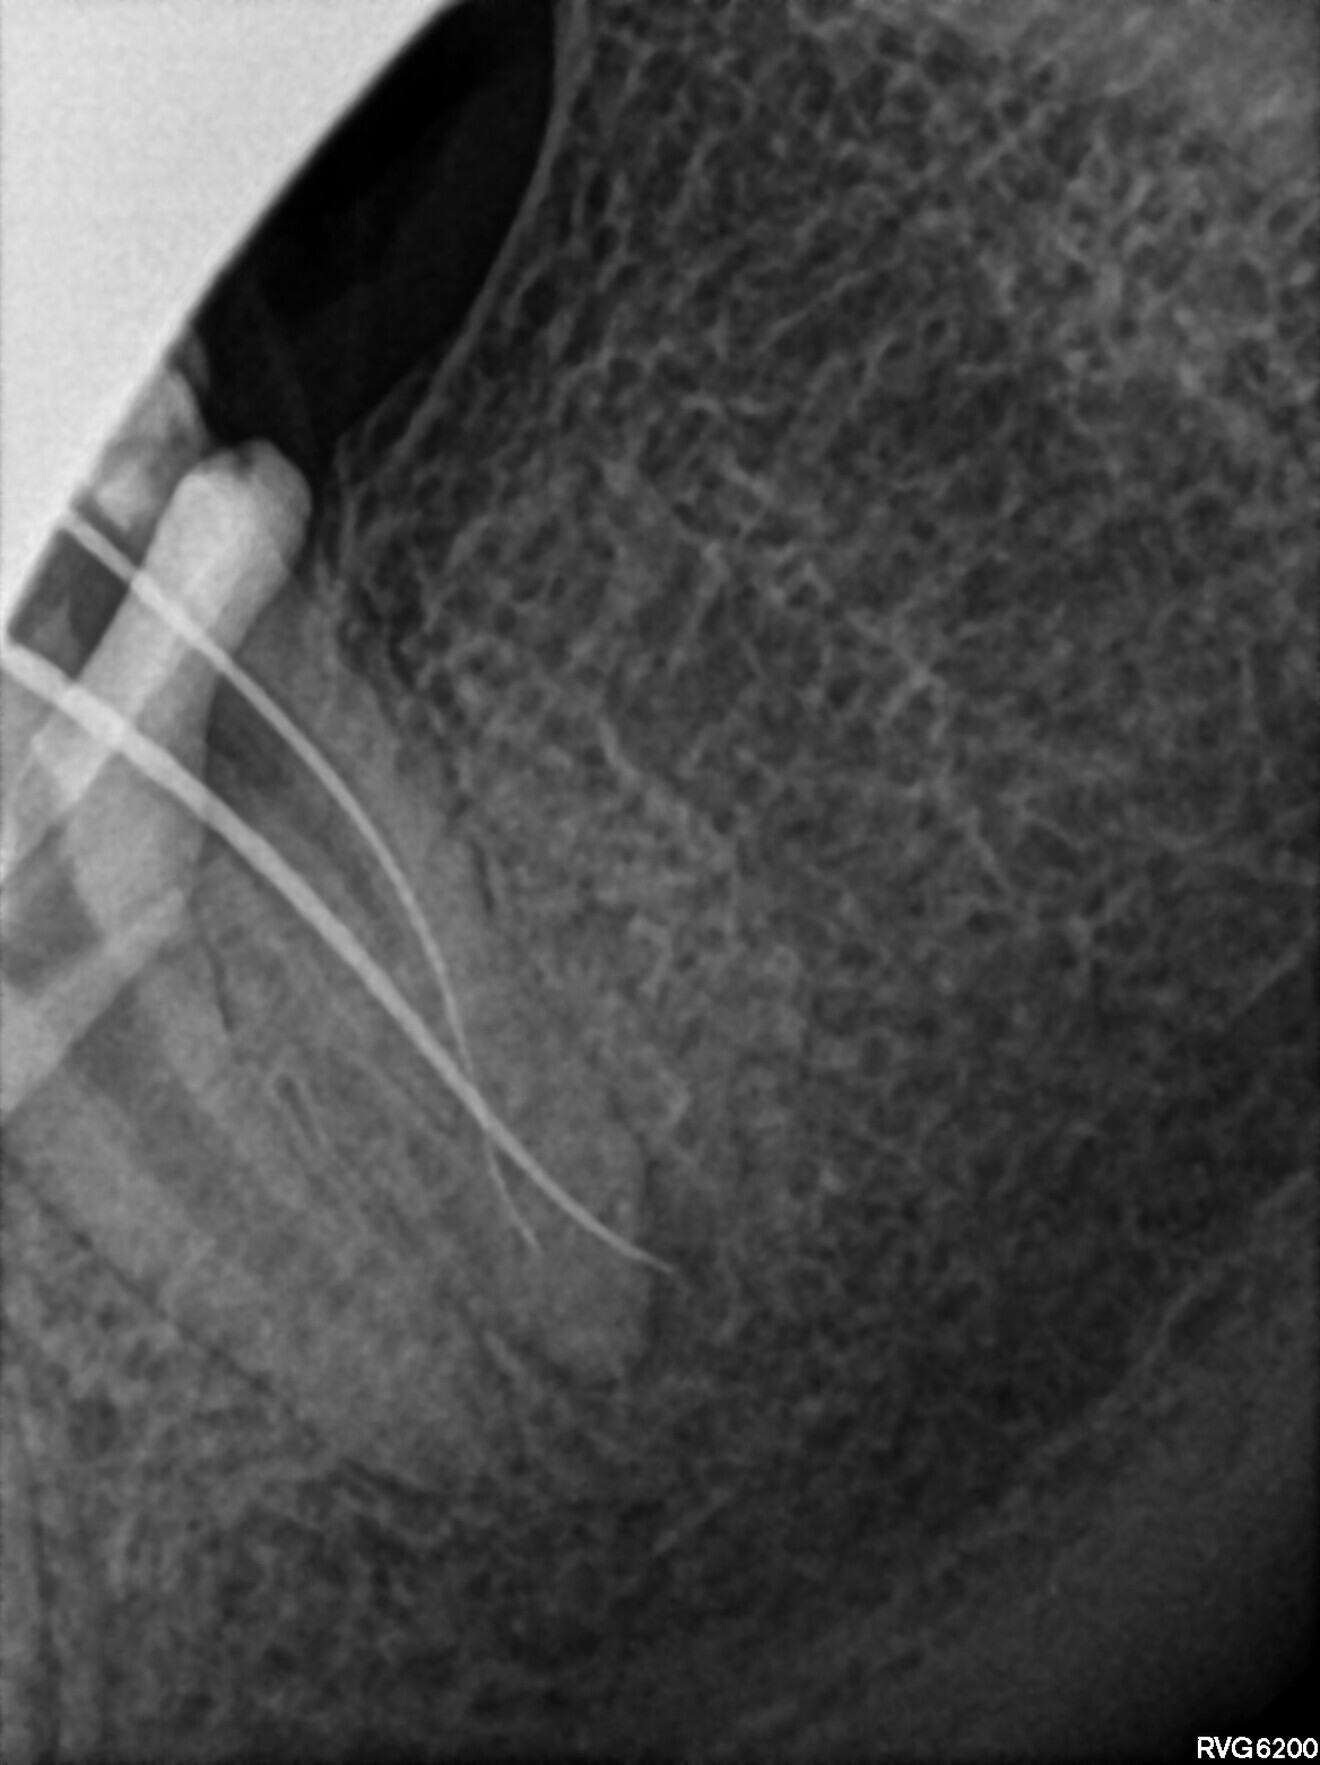

The Less-Prep Endo enhanced irrigation protocol (this protocol was described in an article published inroots, issue 2/2022) was performed using the SkyPulse laser (Fotona) in the AutoSWEEPS (shock wave-enhanced emission photoacoustic streaming) mode. This allowed me to reach the middle third of the MB2 canal with C-PILOT files, and this was confirmed with a radiograph (Figs. 6 & 7). The flow of the irrigants was observed between the MB1 and MB2 canals. A crown-down procedure with the C-PILOT and Perfect Shape files was performed up to the established temporary working length. Owing to a lack of time, the patient was scheduled for another appointment. The tooth was temporarily restored with composite resin.